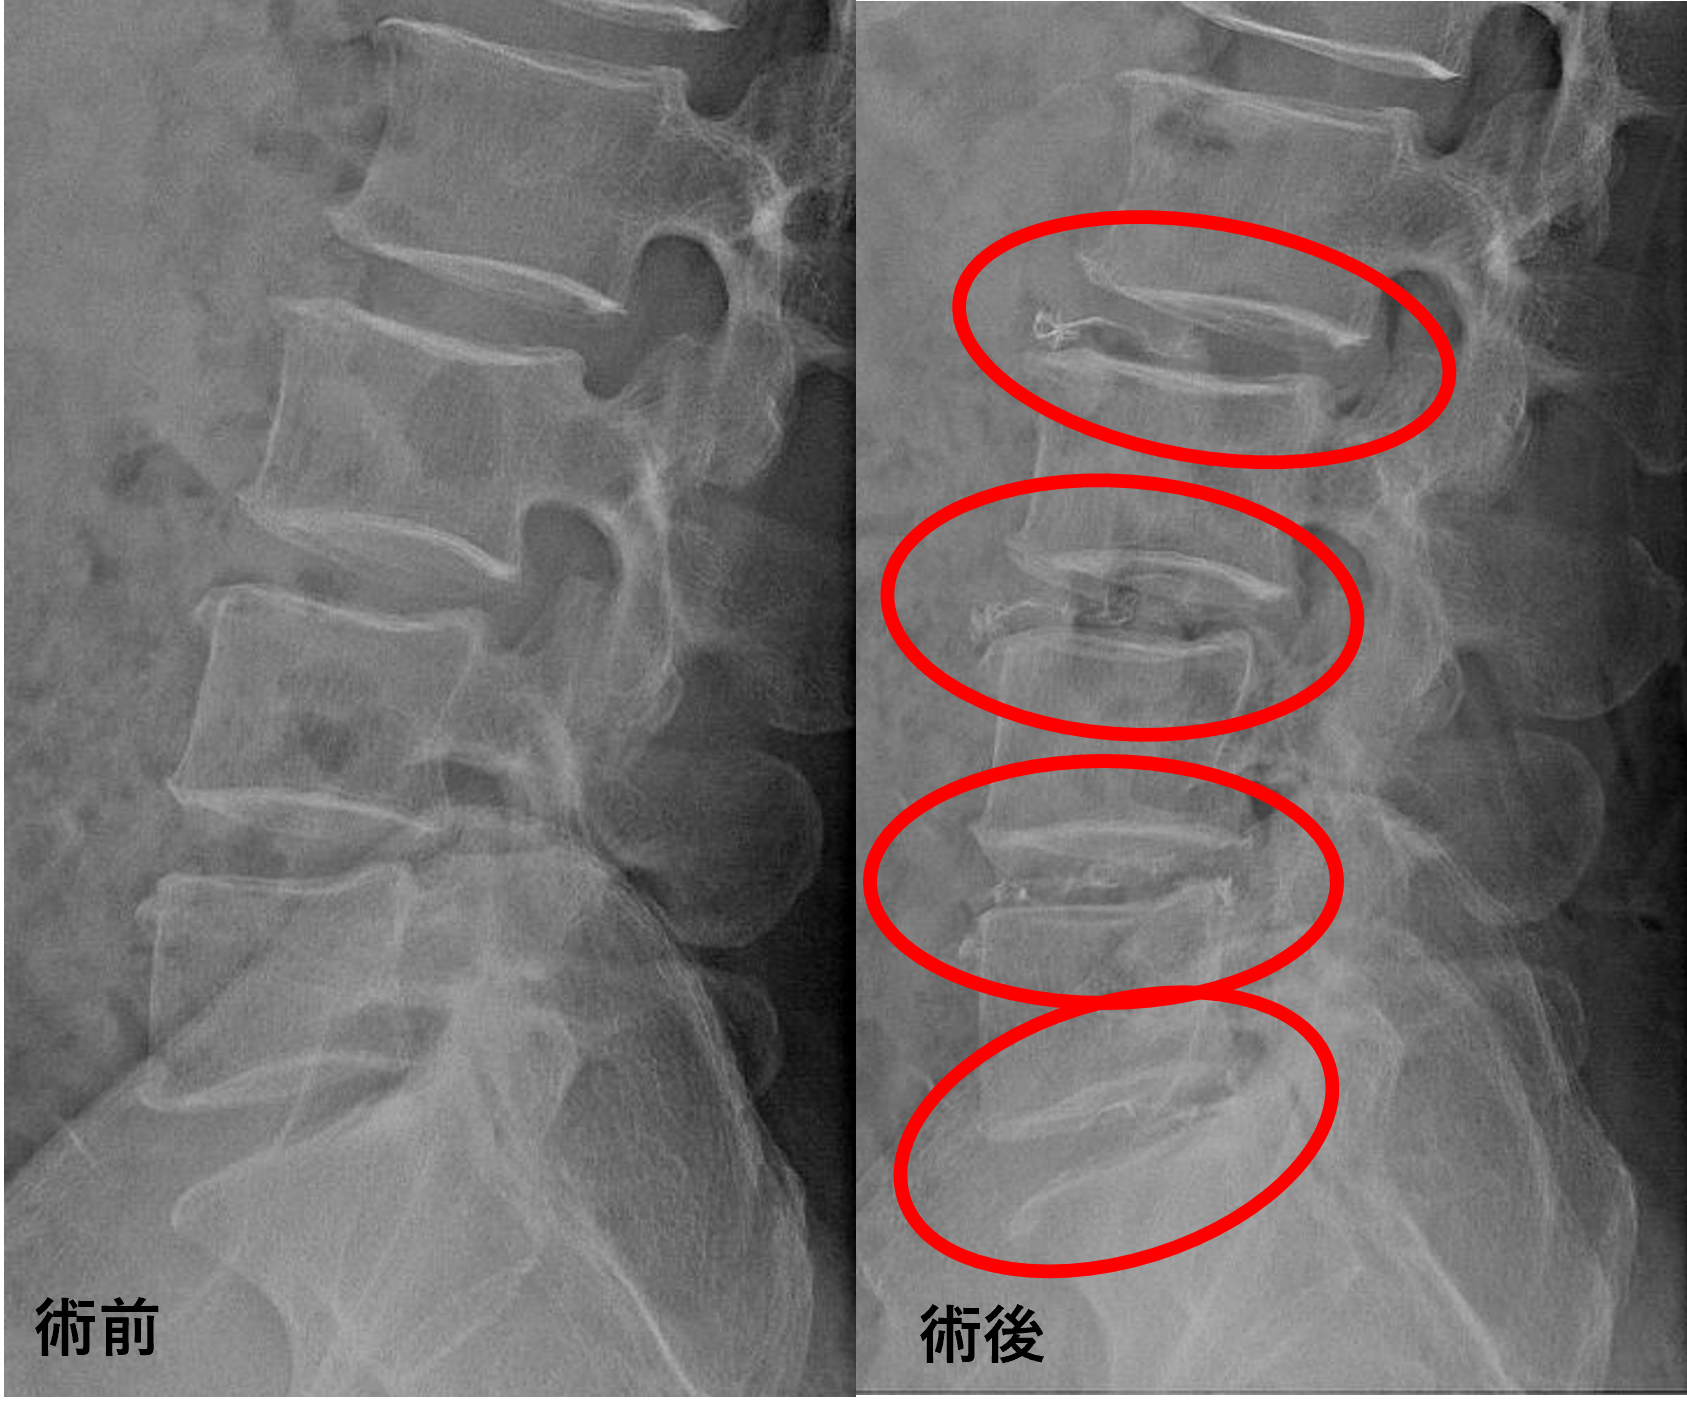

画像及び所見について

- L2/3、5/s – 椎間板変性、膨隆、椎間孔狭窄

- L3/4、4/5 – 椎間板変性、椎間板ヘルニア、椎間孔狭窄

以上のことが画像上認められました。

L2/3、3/4、4/5、5/sの椎間板所見による脊柱管の圧排が、症状の原因の可能性が高い。

患者様と相談の元、L2/3、3/4、4/5、5/sにセルゲル法を施行